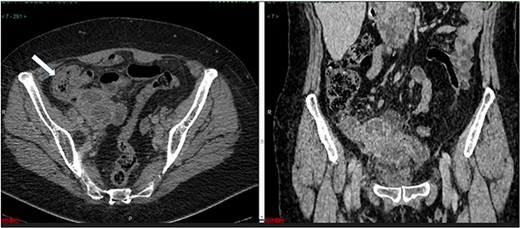

The abdominal computed tomograCT scan showed an enlargement of the cecal appendix with a maximum diameter of 2.8 cm. Irregularities were identified in the lower contour of the appendix, with liquid accumulation and thickened wall measuring 1.6 × 1.4 × 1.1 cm (Fig. 1). Laboratory testing revealed an elevated C-reactive protein level of 216 mg/L and high white blood cells count. Renal function and electrolytes were within the normal range.

(a) Axial CT section of the abdomen showing signs of mucocele of the appendix with intraluminal air. (b) The coronal CT section of the appendix shows that the anterior wall of the appendix had an irregular thickening close to the transition of the middle/distal third.